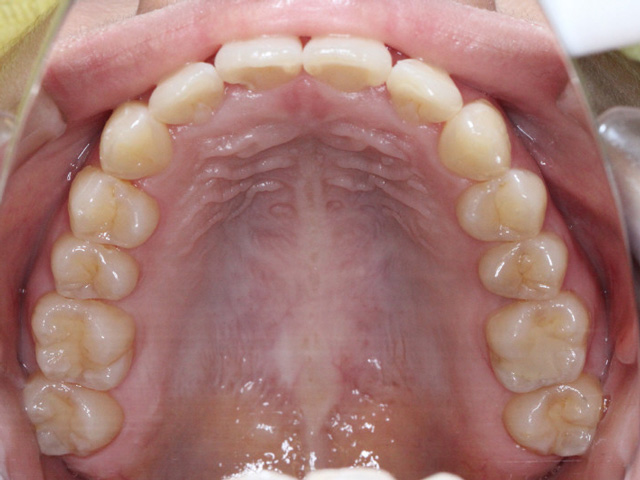

永久歯がすべて生え揃ってから行う大人の矯正とは異なり、顎の成長をコントロールしながら、歯が正しく並ぶための土台を整えていくのが特徴です。

身体全体が「一次成長」と呼ばれる骨格的成長が旺盛な段階なので、それに乗じて顎の骨も成長します。成長段階にある骨は成長が完了した成人と比較すると柔らかく、例えるならまだ固まっていない粘土のような状態です。

そのため、小児矯正では歯列不正(歯並びが悪い状態)を効率良く歯を動かすことが可能で、装置の選択が適切であれば、短い期間で歯並びを改善させることができます。

歯並びを改善させるだけでなく、それと同時に生え変わっていない永久歯が、将来並ぶスペースを確保したり、上下の顎のバランスを整えたりします。

例えば、顎が小さいと、永久歯が生えるスペースが足りず、歯が重なったり、外に押し出されたりします。これを無理に並べようとすると、大人の矯正では抜歯が必要になることもあります。しかし、成長期に顎の幅を広げておけば、そもそも抜歯をしなくても済む可能性が高くなるのです。小児矯正では、装置を使って顎の成長方向を誘導したり、舌や唇の使い方、呼吸の仕方といった口周りの癖を改善することもあります。これらは歯並びに大きな影響を与える要素であり、見過ごされがちですが非常に重要です。